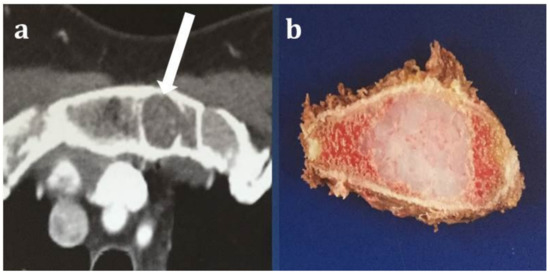

| Tumor location | Costochondral junction | 9/11 (82%) | 10/15 (67%) | 0.804 | 19/26 (73%) |

| Sternum | 2/11 (18%) | 4/15 (27%) | 6/26 (23%) | ||

| Posterior rib | 0/11 (0%) | 1/15 (6%) | 1/26 (4%) | ||

| Tumor size | Mean in mm (range) | 56 (31–151) | 57 (20–127) | 0.435 | 57 (20–151) |

| Character | Lytic only | 0/11 (0%) | 3/15 (20%) | 0.238 | 3/26 (12%) |

| mixed | 11/11 (100%) | 12/15 (80%) | 23/26 (88%) | ||

| Tumor location within the bone | Central | 5/11 (45%) | 7/15 (47%) | 1.000 | 12/26 (48%) |

| peripheral | 6/11 (55%) | 8/15 (53%) | 14/26 (52%) | ||

| Soft tissue mass | No | 3/11(27%) | 1/15 (7%) | 0.279 | 4/26 (15%) |

| Yes | 8/11(73%) | 14/15 (93%) | 22/26 (85%) |